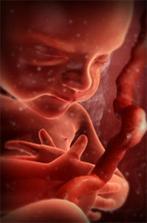

Jak asi víte, těhotenství je členěné na tři časové úseky, kterým říkáme trimestry – každý z nich trvá tři měsíce. Každý z trimestrů je zcela specifický, probíhají v něm určité charakteristické změny, podstupuje se vyšetření a nesou s sebou jiné pocity a obavy nastávající maminky.

zázrak lidské života na videu